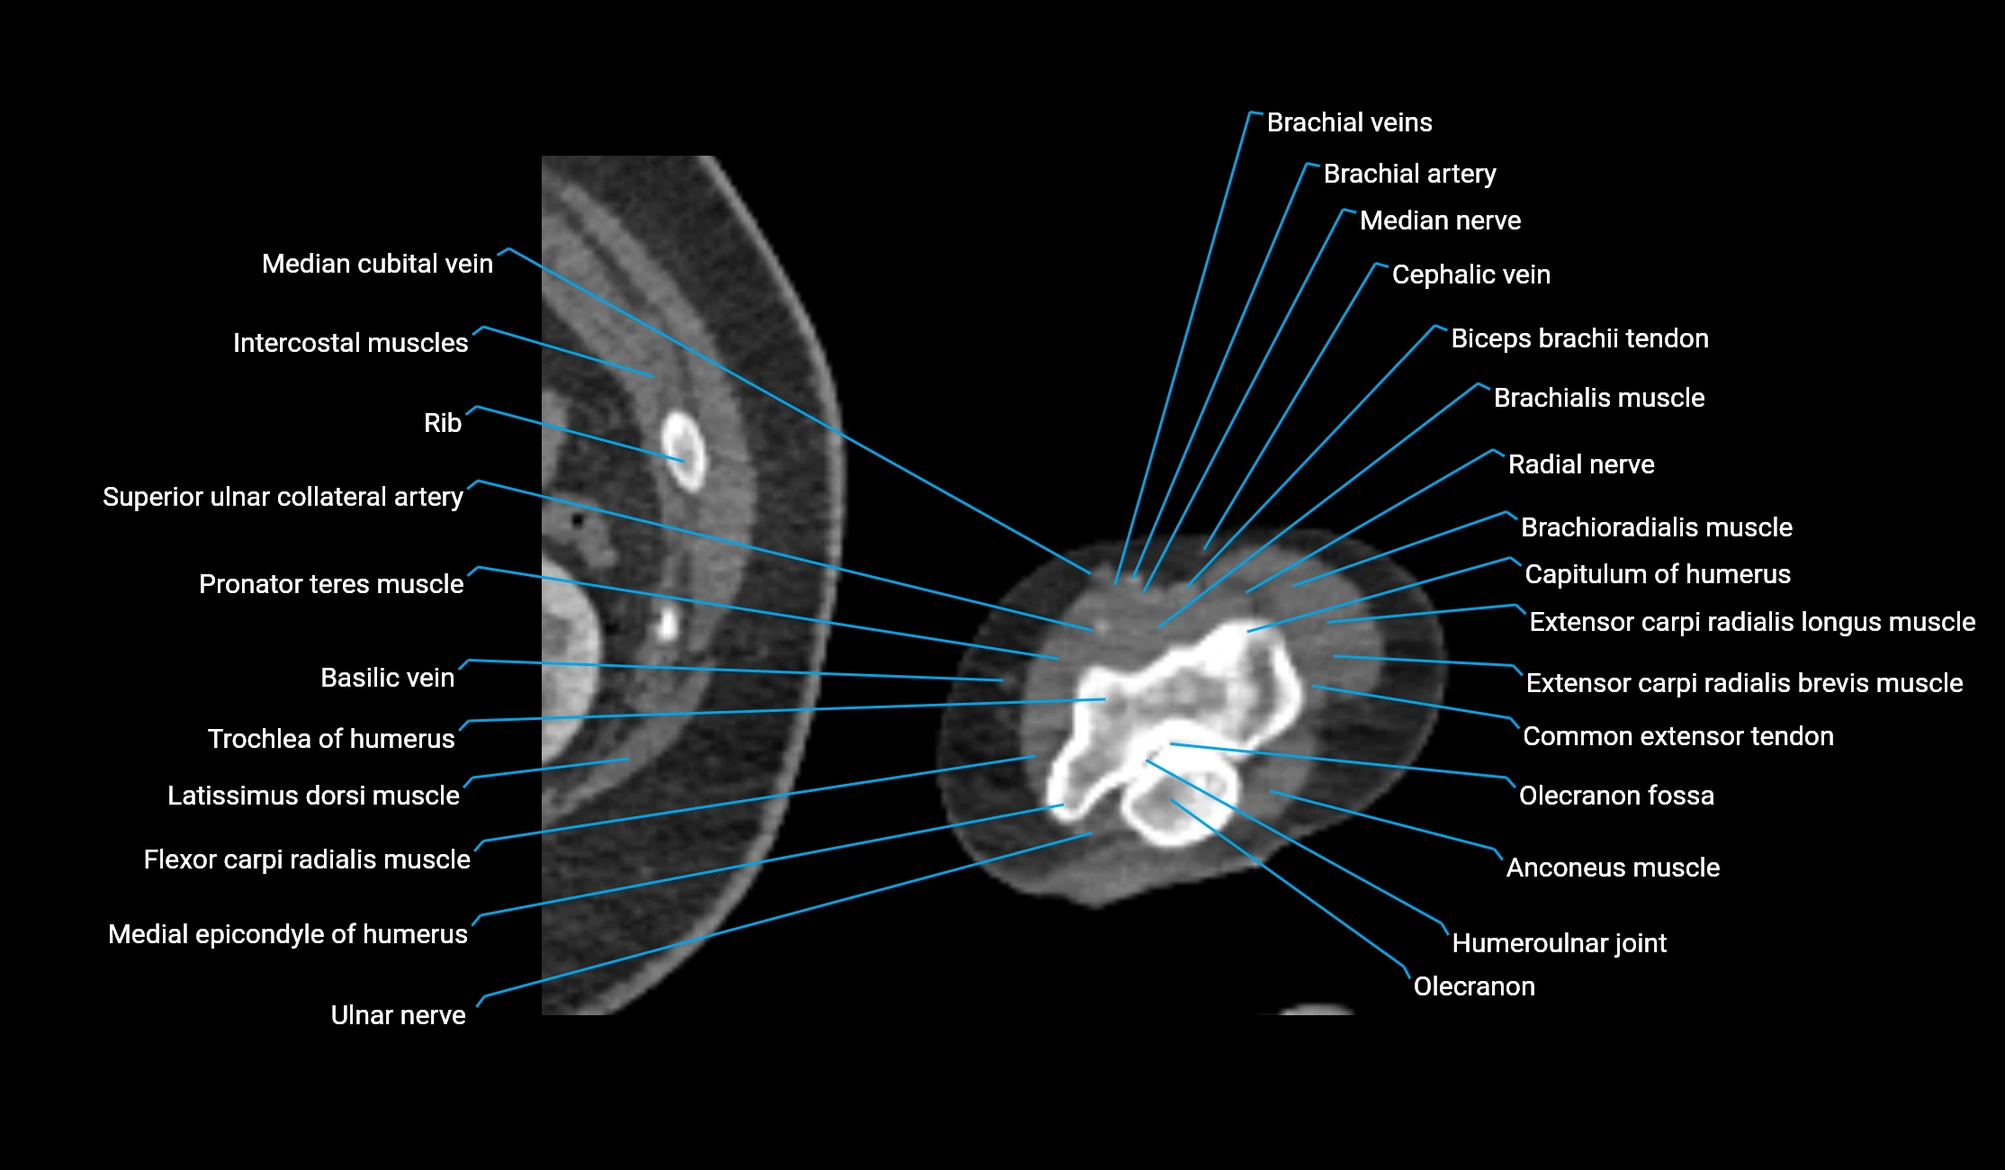

- Anconeus muscle

- Brachioradialis muscle

- Capitulum of humerus

- Common extensor tendon

- Extensor carpi radialis brevis muscle

- Extensor carpi radialis longus muscle

- Flexor carpi radialis muscle

- Humeroulnar joint

- Lateral epicondyle of humerus

- Medial epicondyle of humerus

- Median cubital vein

- Median nerve

- Olecranon

- Olecranon fossa

- Pronator teres muscle

- Superior ulnar collateral artery

- Trochlea of humerus